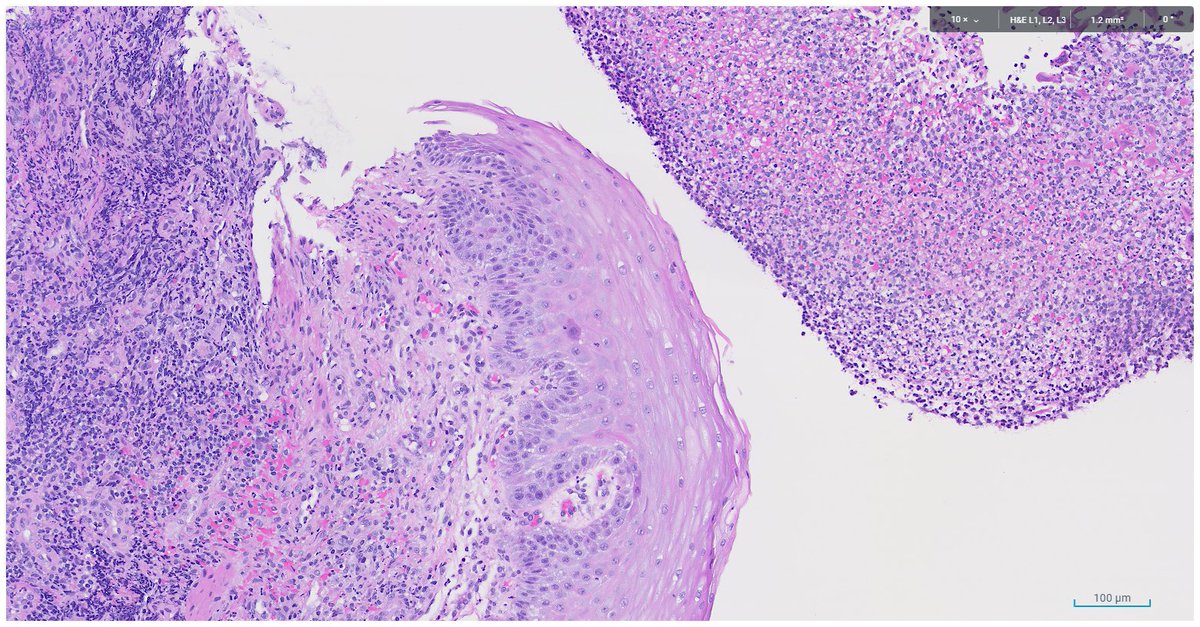

Oxyntic mucosa pseudopolyp. In patients with autoimmune gastritis (pernicious anemia pattern of injury), small foci of undamaged mucosa can appear as polyps because the surrounding mucosa is atrophic and flattened. Krasinskas AM, et al. PMID: 12548171.